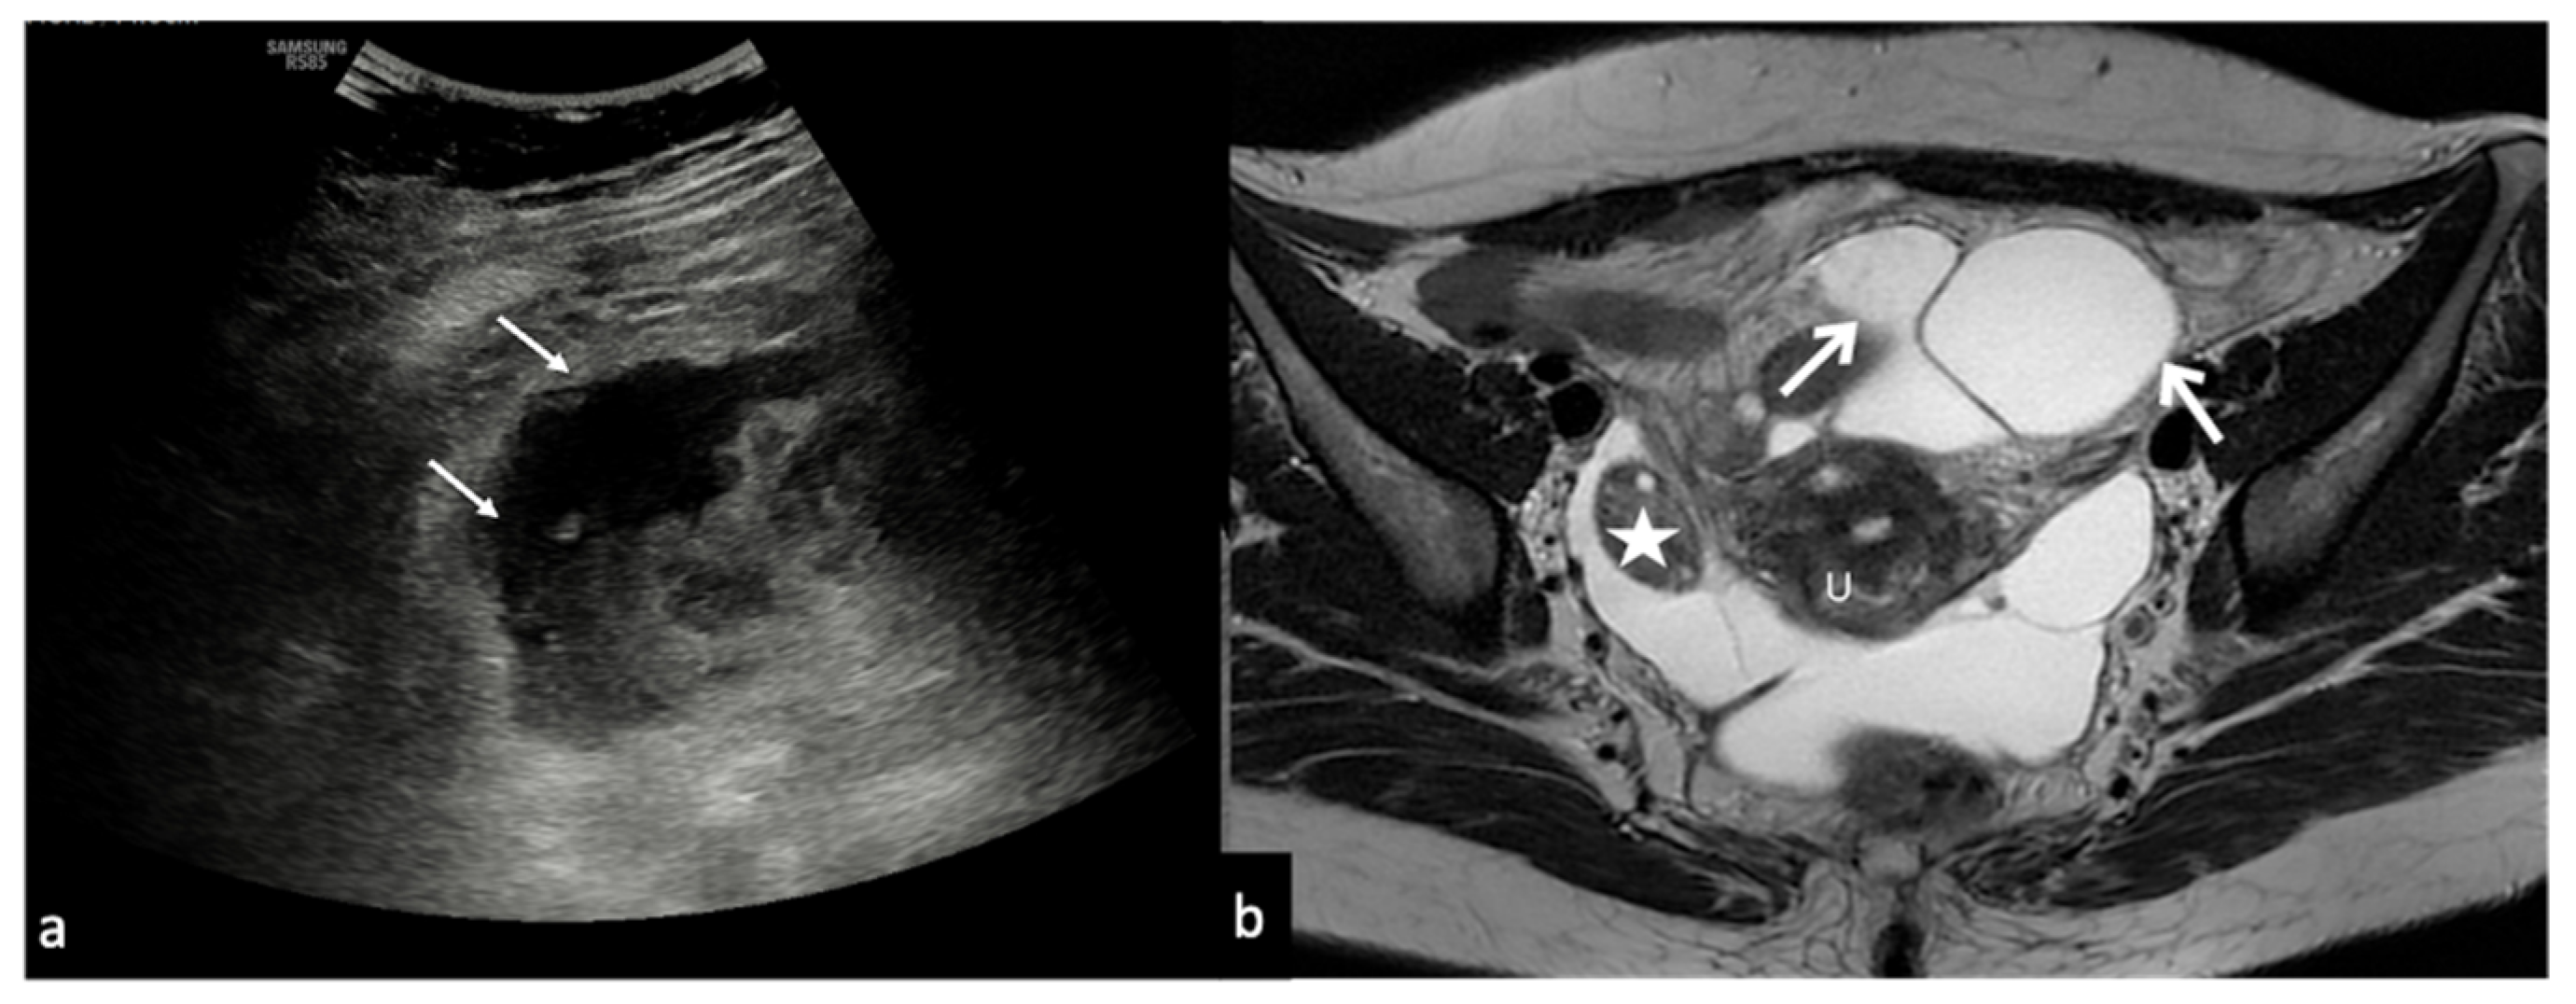

Figure 10. Peritoneal inclusion cyst. TSA–US axial scan (a) shows an irregular, anechoic para-adnexal right fluid collection ((a) arrows). Axial T2w MRI (b) shows a large, well-defined multilocular cystic pelvic mass (arrows). Note several thin internal septa, radiating from the ovary, representing pelvic adhesions. The septa radiate from the ovary (star; (b)). U: uterus.

The imaging features of peritoneal inclusion cysts reflect their pathogenesis and allow for their differential diagnosis from an ovarian cystic mass [20,21]. Indeed, the typical US finding is an ovary trapped inside a cyst, surrounded by septa and fluid. The fluid is usually anechoic but may contain echoes in some compartments due to haemorrhage or protein-rich fluid (Figure 10).

Peritoneal inclusion cysts must also be differentiated from hydrosalpinx, which appears as a tubular or ovoid cystic formation, with visible folds, with no ovary inside of it (Table 8) [1,19,20,21].